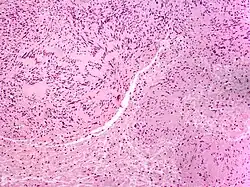

| Solitary circumscribed neuroma | |